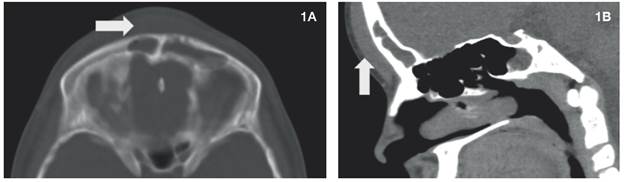

1A y 1B: Tomografia de cráneo corte axial y sagital. Se observa material con densidad de tejidos blandos en seno frontal, con engrosamiento de los tejidos blandos (flechas) y sin erosión de la tabla ósea.

Figura 1: 1A y 1B: Tomografia de cráneo corte axial y sagital. Se observa material con densidad de tejidos blandos en seno frontal, con engrosamiento de los tejidos blandos (flechas) y sin erosión de la tabla ósea.